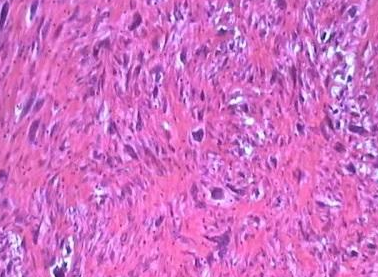

上皮样平滑肌瘤较罕见。瘤细胞呈圆形或多角形,排列成群或条索状,类似上皮细胞,构成肌瘤的部分或全部。...

奇异型平滑肌瘤或称巨细胞平滑肌瘤也是一种罕见的病变。...

高分裂象平滑肌瘤的最大特点是,在显微镜下会发现它的细胞核不是正常的一个,而是分裂成几个。...

富于细胞型平滑肌瘤的外表与普通的子宫肌瘤十分相像,临床表现和大体观与普通肌瘤无区别,只有从显微镜下才就将它辨认出来。...